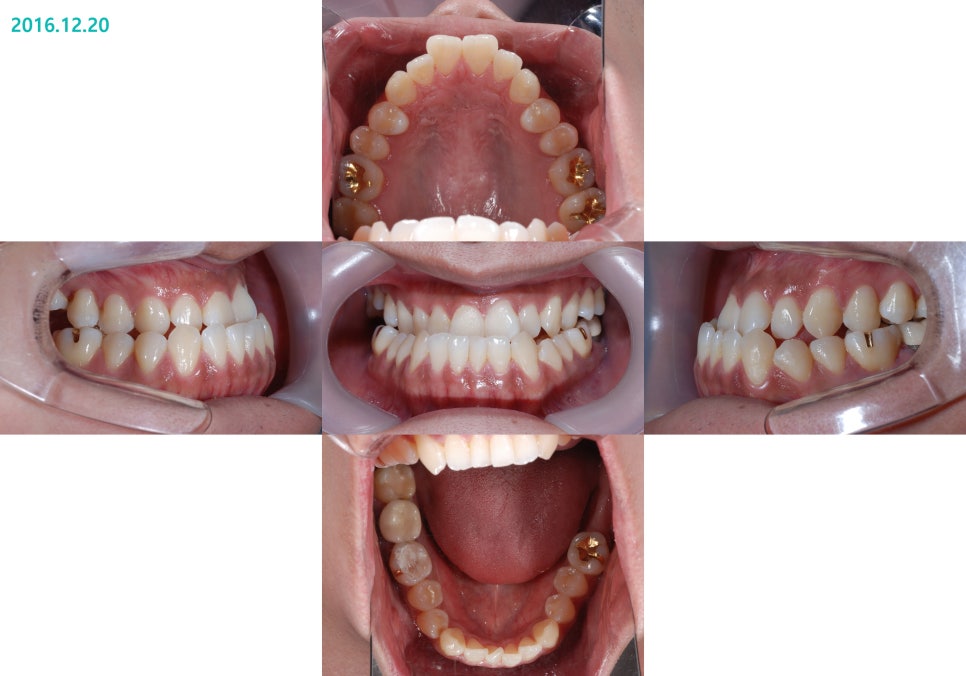

ºñ¼ö¼ú ºñ´ëĪ Ä¡¾Æ ±³Á¤ ÀüÈÄÀÇ »çÁøÀÔ´Ï´Ù.

½ÉÇÑ ÁÖ°ÆÅÎ, ½ÉÇÑ ¾È¸éºñ´ëĪÀÇ

ºñ¼ö¼ú ÁÖ°ÆÅÎ ±³Á¤Ä¡·á Àü

ºñ¼ö¼ú ÁÖ°ÆÅÎ ±³Á¤Ä¡·á ÈÄÀÔ´Ï´Ù.